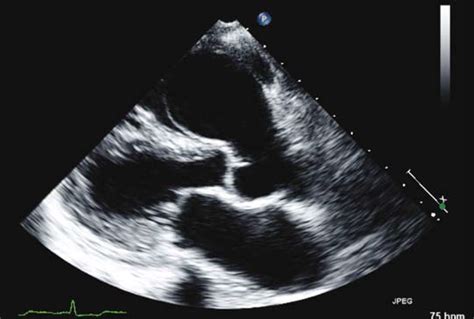

Modern medical imaging has made it significantly easier to identify and characterize an SVA. Cardiologists utilize several non-invasive and minimally invasive techniques to view the structure of the aorta and the integrity of the sinus walls:

Transthoracic Echocardiogram (TTE) The primary screening tool to visualize the aortic root and assess wall motion.

Transesophageal Echocardiogram (TEE) Provides highly detailed images of the sinuses, often used if the TTE is inconclusive.